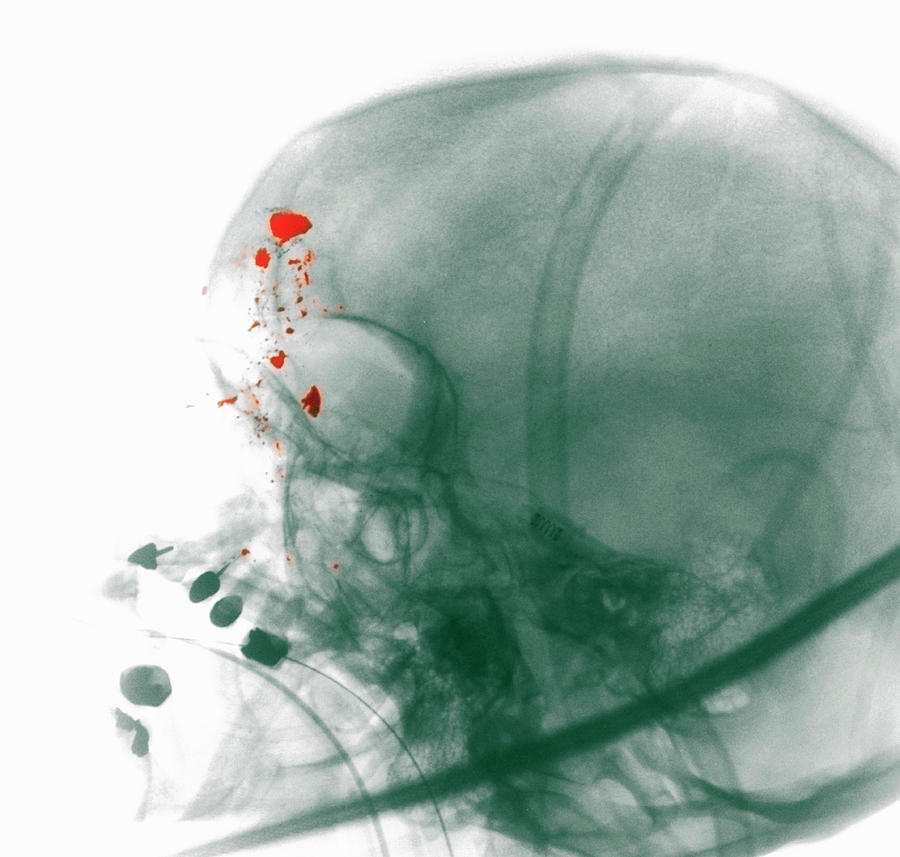

X-ray Showing A Gunshot Wound To The Head Digital Art by Callista …

GUNSHOT WOUND TO HEAD | buyxraysonline

Gunshot Injuries: What Does a Radiologist Need to Know? | RadioGraphics

Gunshot Injuries: What Does a Radiologist Need to Know? | RadioGraphics

Thoracic gunshot wound | Radiology Case | Radiopaedia.org